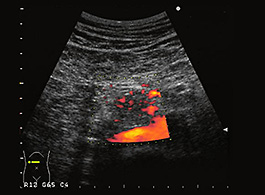

膵嚢胞は、膵臓上または膵臓内にある液体のポケットです。症状がほとんどないため、診断が難しい場合があります。これらは、別の問題の画像検査 ( CT スキャンなど) を実施するときに偶然発見されることがよくあります。

膵嚢胞の可能性が心配な場合は、医師に相談してください。病歴の検査に加えて、CT スキャン、MRI スキャン、超音波内視鏡などのさまざまな検査を実行できます。

検査後、医師は細胞が癌性かどうかを判断するために体液のサンプルを採取することがあります。膵炎が進行している場合は、嚢胞が再発する可能性があることに注意することも重要です。